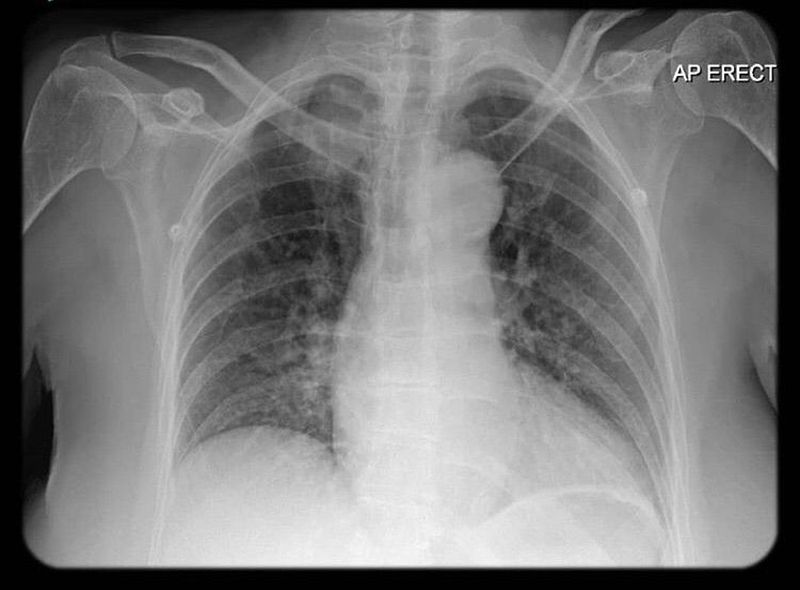

Whats your diagnosis??

CXR

Mediastinal mass

Is left lower lobe collapsed and left clavicle dislocated?

Mediastinitis

The prominent aortic button may indicate hypertension, in a patient with bad habits and / or genetic predisposition an adenocarcinoma in the colon may cause paraneoplastic vasculitis causing the edema in the lung.